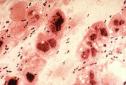

يصيب الالتهاب فصآ كامآ أو جزءآ منه أو أجزاء متفرقة من فصوص مختلفة، وتمتلتيء الحويصلات بالسوائل الالتهابية والصديد، ويمكن أن ينتقل الالتهاب إلى الدم مسببآ ما يسمى (Bacteremia) أو إلى السحايا مسببآ التهاب السحايا (Menengitis)

يتعرض المصابون بنقص المناعة للاصابة بـ التهاب الرئة الفطري ويكون الالتهاب الرئوي في هذه الحالة هو العلامة الاولى لمرض نقص المناعة، والفطر المسبب للمرض هو غالبآ (Pneumocystis Carinii)